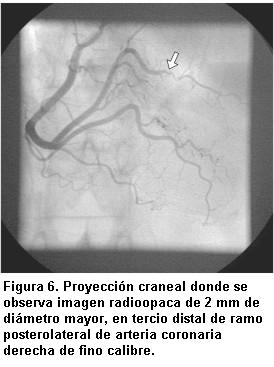

La misma evidenció imagen radioopaca de 2 mm de diámetro mayor, en tercio distal del ramo posterolateral de la arteria coronaria derecha de fino calibre, que no obstruye el flujo pero que compromete severamente su luz, sin otras lesiones coronarias (figura 6).

Se interpreta como una embolia séptica a punto de partida de endocarditis infecciosa, por lo que no se realiza angioplastia coronaria y se solicita consulta con equipo de cirugía cardíaca. Estando en sala de hemodinamia se coloca con éxito, por acceso femoral derecho, marcapaso percutáneo transitorio (figura 7).